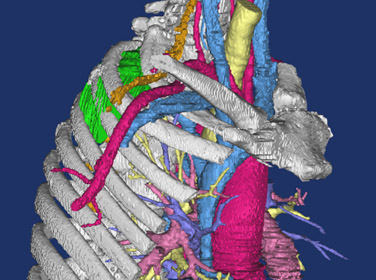

In complex cases, standard two-dimensional (2D) computed tomography (CT) images have limitations in their ability to demonstrate anatomical relationships in preparation for surgery. Three-dimensional (3D) printed anatomic models, using imaging data from high resolution CT scans, provide higher-level understanding of potential anatomic challenges. This is particularly true in patients with complicated past surgical history or pathology. Due to the unique characteristics of the esophagus, specialized techniques are necessary to enhance the quality of the 3D printed model of the esophagus.

The Mayo Clinic, Rochester, Minnesota, has utilized 3D printing since 2006, with over 130 models printed throughout all surgical specialties. For patients with complex esophageal pathology, a unique application of an oral effervescent agent is combined with a positive enteric contrast agent to distend the esophageal lumen during CT scanning in order to facilitate esophageal segmentation during post-processing. This optimizes visualization of abnormal esophageal anatomy and the relationship to adjacent mediastinal structures. 3D anatomic models are printed using imaging data from each individual patient’s CT scans. The data is segmented and processed using proprietary software, and then converted into a stereolithography (STL) file. The STL file is sent to the 3D printer (Stratasys Connex 350 polyjet), and a model is created using liquid polymers. The reconstructions are used for multi-disciplinary pre-operative discussions, surgical planning, and as part of the patient education and consent process.

This video presents the utility of 3D printing to individualize management of complex esophageal pathology in two recent patients. The author performed a combined endoscopic and surgical procedure in a male patient with metastatic teratoma leading to a left pneumonectomy, complicated by an esophago-aortic fistula requiring aortic bypass and esophageal diversion without resection. 3D printing enabled visualization of his native esophagus, and allowed EMR of his esophagus via a transgastric stent with concomitant hiatal dissection, and transection of the GEJ. He recovered well, and esophageal reconstruction is planned. In the second patient, 3D printing allowed enhanced visualization of multiple esophageal diverticula in order to plan for the most appropriate surgical approach. The proximal extent of the diverticula was determined and the relationship to surrounding anatomy better elucidated.

3D printed anatomic models are valuable tools when endoscopic or surgical intervention is planned in patients with complex esophageal pathology or anatomy. The author recommends ingestion of an oral effervescent agent in order to optimize the quality of esophageal imaging for these models, allowing for full appreciation of anatomical relationships. The printing of 3D anatomic models allows all members of the multi-disciplinary team to plan for the appropriate surgical approach, prepare for the intervention, and anticipate potential difficulties. The models also give each patient invaluable insight into their condition, and allow them to be fully involved in complex discussions regarding their care.